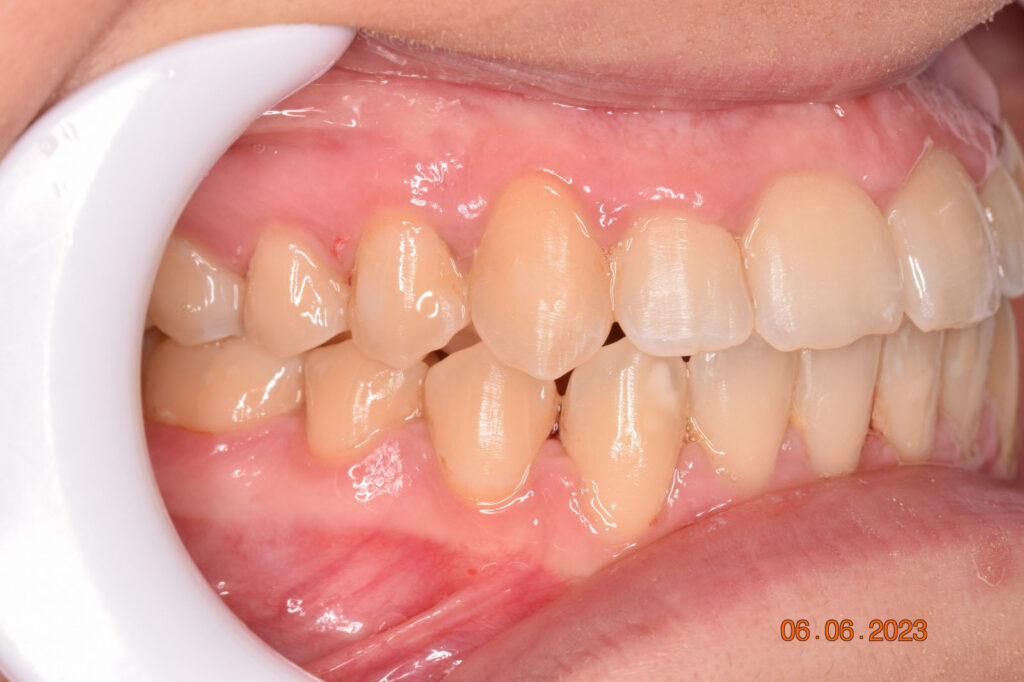

A 27-year-old female patient presented with class III malocclusion, 15 mm crowding in the upper arch, an anterior open bite, a lateral crossbite, and a total ABO score of 29. Her facial profile was straight with a retrusive maxilla, and the upper and lower incisors were retroclined. An extreme lack of midface support was also noted, and the constricted dental arches resulted in a poor smile width and dark buccal corridors. No myofunctional investigations were performed at the time, as they were initially considered unnecessary.

The treatment began in 2017. Given the patient’s preference for less visible brackets, Damon Clear brackets were selected. High torque upper cuspids and low torque upper incisors were chosen to offer the best torque control for upper arch development. For the lower arch, there were no alternative bracket configurations available. Bite turbos were applied to the upper second molars.